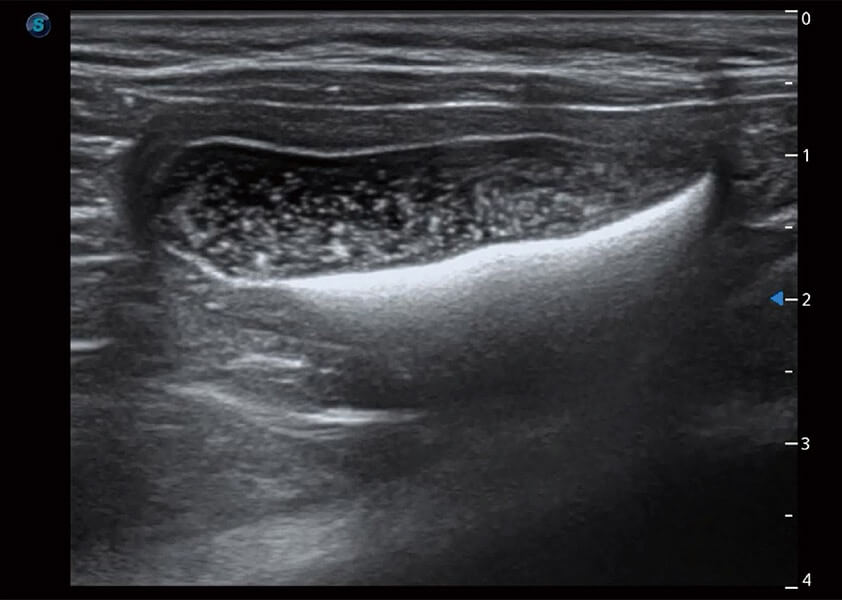

ProPet 60 作为一款高端台式动物超声设备,为动物医生的日常诊断提供了一系列贴合动物临床需求、解决临床实际问题的高级成像功能。凭借全系列高清探头,满足医生对腹部、心脏、生殖、浅表、肌骨等成像的所有需求,切实帮助您提升检查效率,提高诊断信心。

动物是人类最亲密的朋友和最值得信赖的伙伴。DB中国旗舰官方网站也一直致力于探索动物专用的超声影像解决方案。 全新推出的ProPet系列,是DB中国旗舰官方网站在动物超声影像智能化、专业化、精准化的一次跨越式革新。动物不能用言语来表述自己的不适,通过超声影像,ProPet系列搭建了动物医生与不同物种沟通的“桥梁”,为动物医生注入了“治愈之力”。